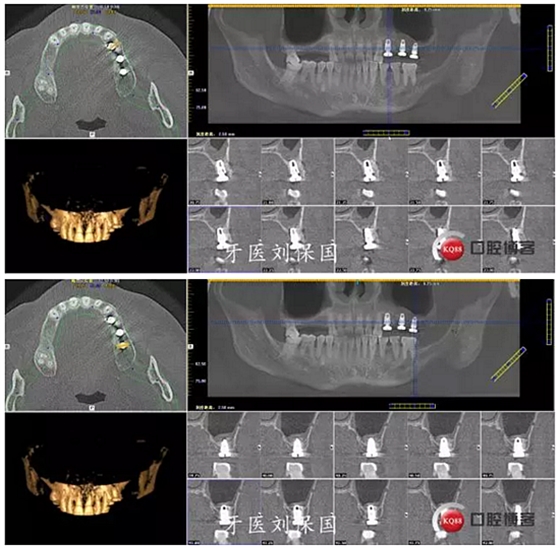

3.術(shù)后CT:

4.六個(gè)月后二期CT: